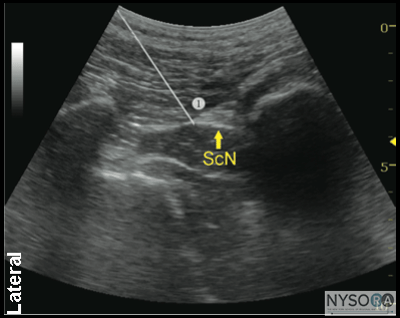

Figure 2-4: Transgluteal approach to sciatic block; patient position, transducer (curved) placement and needle insertion. Distribution of Blockade Sciatic nerve block results in anesthesia of the entire lower limb below the knee, both motor and sensory blockade, with the exception of a variable strip of skin on the medial leg and foot, which is the territory of the saphenous nerve, a branch of the femoral nerve. In addition, both the transgluteal and subgluteal approaches provide motor blockade of the hamstring muscles. The skin of the posterior aspect of the thigh however, is supplied by the posterior cutaneous nerve of the thigh, which has its origin from the sciatic nerve more proximal than the subgluteal approach. It is, therefore, unreliably anesthetized with subgluteal block; however, it is of relatively little clinical importance. ![]() Figure 2-5: Sciatic nerve (yellow arrows) as seen in the subgluteal position (linear transducer), needle path (white arrows) and local anesthetic (turquoise arrows) in the intramuscular tunnel surrounding the sciatic nerve. Equipment Equipment needed is as follows:

Technique The description of the technique in this chapter will focus primarily on the transgluteal approach. However, since the subgluteal approach is performed just a few centimeters more distal and it is technically easier, the reader can easily perform either approach by using general guidelines provided and referring to Figure 2-3, Figure 2-4, and algorithms at the end of the chapter. With the patient in the described position, the skin is disinfected and the transducer is positioned so as to identify the sciatic nerve (Figure 2-4). If the nerve is not immediately apparent, tilting the transducer proximally or distally can help improve the contrast and bring the nerve “out” of the background of the musculature. Often, the nerve is much better imaged after the injection of local anesthetic (Figure 2-5). Alternatively, sliding the transducer slightly proximally or distally can improve the quality of the image and allow for better visualization. Once identified, the needle is inserted in-plane, typically from the lateral aspect of the transducer and advanced toward the sciatic nerve. If nerve stimulation is used (1.0 mA, 0.1 msec), the passage of the needle through the anterior fascial plane of the gluteus muscles often is associated with a motor response of the calf or foot. Once the needle tip is positioned adjacent to the nerve (Figure 2-6A) and after careful aspiration to rule out an intravascular needle placement, 1 to 2 mL of local anesthetic is injected to document the proper injection site. Such injection often displaces the sciatic nerve away from the needle; therefore, an additional advancement of the needle 1 to 2 mm toward the nerve may be necessary to ensure the proper spread of the local anesthetic. When injection of the local anesthetic does not appear to result in a spread around the sciatic nerve, additional needle repositions and injections may be necessary. Assuring the absence of high resistance to injection is of utmost importance because the needle tip is difficult to visualize on ultrasound due to the steep angle and depth of the needle placement.

Figure 2-6: (A) Ultrasound image demonstrating the simulated needle path to reach the sciatic nerve (ScN) using an in-plane technique in transgluteal approach. The simulated needle (1) is shown transversing the gluteus muscle with its tip positioned at the lateral aspect of the sciatic nerve. (B) Needle path and distribution of local anesthetic (blue shaded area) to block the ScN through the transgluteal approach. In an adult patient, 15 to 20 mL of local anesthetic is usually adequate for successful blockade of sciatic nerve (Figure 2-6). Although a single injection of such volumes of local anesthetic suffices, it may be beneficial to inject two to three smaller aliquots at different locations to ensure the spread of the local anesthetic solution around the sciatic nerve.